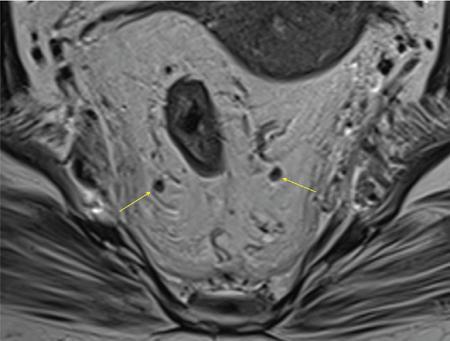

Sumit Mukhopadhyay, Saugata Sen, Aditi Chandra, Argha Chatterjee, Priya Ghosh, Anisha Gehani Cloaca is the part of hindgut caudal to the attachment of the allantoic diverticulum. It divides into a broad anterior urogenital (vesicourethral and urogenital sinus) part and a narrow posterior anorectal compartment/primitive rectum, separated by the urorectal septum. This anorectal compartment gives rise to mid rectum and lower rectum and upper part of anal canal proximal to dentate line. The peritonealized upper part of rectum develops from hindgut proximal to cloaca. The distal most part of anal canal below the dentate line develops from invaginated ectoderm known as proctodeum (Fig. 8.5.1). Initially during development, the rectum is suspended from the posterior abdominal wall by a mesentery, along with the rest of the gut. After completion of rotation of the gut, rectal mesentery fuses with the posterior abdominal wall, majority of rectum becomes retroperitoneal and hindgut mesentery is seen as mesorectum. The artery of the hindgut is inferior mesenteric artery. Anatomically, classically taken as 6 inches (approximately 15 cm), or beginning at the level of S3 vertebra. Surgically defined as 15–18 cm from anal verge (AV), thus anal canal and rectum are considered together for the purpose of surgical and radiological anatomy, though management differs in cases of rectal adenocarcinoma and anal squamous cell carcinoma (SCC). Various trials on rectal cancer neoadjuvant therapy have taken different lengths of cut-off for rectal cancer starting from AV: 9 cm, 12 cm, 15 cm or 16 cm (Table 8.5.1). Rectum continues as sigmoid colon superiorly. The point of transition between rectum and sigmoid colon is controversial. Anatomically, this is the point where sigmoid mesocolon ends, appendices epiploicae are lost and taenia coli gradually converge and disappear. There is no single transition point between these features. These features are not visible to the radiologist/endoscopist as well. Several features defining rectosigmoid junction/transition are variously accepted by different radiologists: Rectum continues as anal canal, which opens to the exterior at AV (mucocutaneous junction). Anorectal junction (ARJ) is considered to be the point at which the angle of the long axis changes, and corresponds to the upper border of puborectalis muscle. The change in axis of anal canal and rectum is well visualized on sagittal MRI. Dentate line lies along the anal crypts (the openings of anal glands), and vertical folds called columns of Morgagni extend superiorly from the dentate line. Anatomists consider the dentate line to be the landmark for ARJ, but the dentate line lies distal to the puborectal sling, and this definition is not clinically relevant. Anal canal is directed posteroinferiorly. At ARJ, the long axis of rectum changes so that it is directed anteroinferiorly. Mid rectum and upper rectum follow the sacral concavity, and the long axis of rectum is again directed posteroinferiorly. Upper rectum is frequently mobile and may not be in midline. Three incomplete folds consisting of mucosa, submucosa and circular muscles, named as Valves of Houston, are seen within the lumen of rectum during endoscopy, but these are not visualized radiologically. The middle valve is roughly at the level of anterior peritoneal reflection, and the superior most valve is at the level of rectosigmoid junction. Surgically and radiologically, rectum is divided into thirds: lower third, middle third and upper third (Table 8.5.2). Most commonly, this division is according to distance or length from AV. Lower third is 0–5 cm, middle third is 5–10 cm, upper third is 10–15 cm from AV (Fig. 8.5.6). Some radiologists define low rectum as 6 cm or less from AV, mid rectum as 7–11 cm and upper rectum as 12–15 cm. The justification of defining low rectum as 6 cm or less from the AV is that, management of most of the tumours at this location suffers from surgical challenges due to tapering of mesorectum and proximity of other pelvic structures. These tumours have a higher rate of CRM positivity, abdomino-perineal resection (APR) and permanent stoma, higher rates of recurrence and mortality, poor function of stoma after sphincter preservation. Another way of defining low rectum, surgical management of which differs from the upper two-thirds, is the portion lying distal to the proximal origin of levators at pelvic side wall. This definition was provided by the English National Low Rectal Cancer Development Programme (LOREC) and is best visualized in the coronal plane by a line joining proximal origins of levators at pelvic side walls (Fig. 8.5.7). ARJ is an important landmark in the management of rectal cancer. Distance between lower border of the tumour and ARJ is important for treatment planning. ARJ is defined as the point at which puborectalis fuses with the levator muscles, and the long axis of rectum changes from anteroinferior to posteroinferior at this point. Its upper extent begins few centimetres above the dentate line, and its length varies from 2–5 cm from AV. Histologically the proximal end of the anal canal is the point at which the columnar epithelium of the rectum becomes the transitional epithelium. Anal canal mucosa has several longitudinal columns, known as anal columns, which end at the dentate line. Below the dentate line the mucosa is smooth and transitions into skin at AV. Approximately at the level of dentate line, the internal anal sphincter (IAS) ends, and the smooth mucosa leads to the intersphincteric plane, distal to which the external anal sphincter extends up to the AV (Fig. 8.5.8). Upper third of rectum is anteriorly covered by peritoneum. Peritoneal covering gradually widens superiorly till it is covered by peritoneum on all sides at the level of sigmoid colon. The exact level of peritoneal reflection varies between individuals, and is quite often seen in axial and sagittal MRI. In axial T2-weighted MRI, a thin hypointense layer with V-shaped attachment to anterior rectal wall is seen representing the anterior peritoneal reflection. This is known as the ‘sea-gull’ sign. Mesorectum and mesorectal fascia (Fig. 8.5.10): lower two-thirds are surrounded by extraperitoneal fat and connective tissue known as mesorectum, which contains lymph nodes, nerves and blood vessels (descending branches of superior rectal artery and corresponding veins). Mesorectal fat is contained within a thin layer of fascia, known as mesorectal fascia (MRF). MRF separates mesorectal fat from extra mesorectal tissues of the pelvis. A relatively avascular plane of areolar tissue lies between MRF and parietal pelvic fascia, facilitating surgery. Importance: Assessment of structures within mesorectum is important for staging and prognostication of rectal cancer. Mesorectal node involvement is N disease. Tumour extension within mesorectal vessels is known as extramural vascular invasion (EMVI) and is thought to be associated with higher chances of vascular dissemination and distant metastases. MRF forms the boundary of the surgical excision plane in total mesorectal excision (TME) – the standard surgery for rectal cancers at present. It is important to understand the various fascial reflections of the pelvis in order to understand pathways of disease spread. The plane between the MRF and the pelvic fascias is the surgical plane. Posteriorly, covering the sacrum, presacral venous plexus and hypogastric nerves, lies the presacral fascia. It fuses with MRF inferiorly at the level of levator ani muscle. The space between presacral fascia and MRF is known as the retrorectal/rectosacral/pelvirectal space, and that between the sacrum and presacral fascia is the presacral space. The presacral fascia continues laterally as the parietal pelvic fascia which covers the lateral pelvic wall. It has two lamellae which encase the pelvic visceral nerves as they course forward from the sacrum to the anterior pelvic organs. The rectosacral fascia/Waldeyer fascia, called as rectosacral ligament by anatomists, is a thickening arising from presacral fascia and running forward to meet the MRF. This divides the rectosacral space into a superior and an inferior compartment, communicating with each other. In males, anteriorly, between the rectum and prostate-seminal vesicles, lies the rectoprostatic fascia/Denonvillier fascia. It is difficult to distinguish from the closely related MRF, and carries the hypogastric nerve and vascular branches to the prostate and male genital organs. In females, anterior to the MRF, lies the rectovaginal septum. According to most views, this septum consists of two layers. The anterior layer corresponds to Denonvillier fascia, and extends from the pelvic floor to the posterior wall of vagina and uterus. The posterior layer is in close relation to the MRF, runs from the pelvic diaphragm and ascends to the peritoneal reflection before fusing with the rectal wall. The lateral rectal ligaments are controversial structures as they are not visualized by imaging and may not carry important structures such as nerves and vessels. However, in some cases, the middle rectal artery may run through them and the accompanying lymphatics may provide a pathway between mesorectal and extra mesorectal lymph nodes. In females, the pelvic floor may be considered to have three compartments, anterior compartment containing bladder and urethra, middle compartment containing the vagina and the posterior compartment containing the rectum. These compartments are supported by the endopelvic fascia and levator ani muscle. The levator ani has several compartments, of which the two most important ones are the iliococcygeus and puborectalis. The iliococcygeus starts as the same fibres as the EAS, and then fans out as a sheet to insert at the pelvic sidewall at the tendinous arch. Posteriorly these fibres fuse in the midline to form the levator plate/raphe. The pubococcygeus and puborectalis are considered together as pubovisceralis muscle. It inserts lateral to the symphysis pubis anteriorly, and forms a sling around the rectum, pulling it anteriorly. Components of the levator ani can be identified in T2-weighted MR images. In males, there are two compartments, anterior containing bladder, urethra, prostate and seminal vesicles and the posterior compartment containing the rectum. Pubococcygeus consists of pubourethralis and puborectalis in males. In sagittal images, the pubococcygeal line is an important reference line, drawn from the inferior border of symphysis pubis to the last joint of the coccyx, representing the level of pelvic floor. The H line is drawn from the inferior aspect of the symphysis pubis to the posterior wall of the rectum at the level of ARJ. This represents the anteroposterior width of the levator hiatus, and upper limit of normal is 5 cm. The M line is the vertical descent of the levator hiatus, drawn as a perpendicular line dropped from the pubococcygeal line to the posteriormost aspect of the H line, and should measure maximum 2 cm. The angle of the levator plate and the pubococcygeal line is also measured. In axial images, the entire normal levator is of uniform thickness and homogeneous low signal intensity. Coronal images show intact iliococcygeus muscle which is convex upwards. The upper half of the anal canal proximal to the pectinate line, the IAS, the conjoint longitudinal coat and the rectum drain lymph upwards into the mesorectal nodes (Fig. 8.5.11) and then lymphatics follow the superior rectal artery into the inferior mesenteric group of lymph nodes. The lymph from these nodes is carried by the intestinal lymph trunk(s). Anal canal below the dentate line along with the EAS drains to the superficial inguinal nodes. Lymphatic vessels also travel with the median sacral artery and drain the puborectalis muscle before finally joining the internal iliac lymph nodes. The internal iliac lymph nodes drain into pre-aortic and paraaortic (lumbar) lymph nodes and efferents from the nodes form the lumbar trunks. The intestinal trunks and the lumbar trunks enter the abdominal confluence of the lymph trunks at the level of the L1–L2 vertebrae, called the cisterna chyli, and then ascend as the thoracic duct. The pelvic lymph nodes lying outside the mesorectum are termed as ‘extra mesorectal lymph nodes’. Above the dentate line: blood supply is from the superior rectal artery, which originates from the inferior mesenteric artery, a branch of abdominal aorta. Superior rectal artery passes in the sigmoid mesocolon and divides into two branches behind the rectum at the level of S3 sacral segment. The superior rectal artery ends in the anal columns by forming a rich vascular plexus/anastomosis with the branches of inferior rectal artery. Blood returns via the superior rectal veins into the inferior mesenteric vein, which drains into the splenic vein and eventually into the portal venous system. Below the dentate line, the inferior anal canal obtains its blood supply from the inferior rectal artery, which is a branch of internal pudendal artery, originating from the anterior division of internal iliac artery. Blood returns via the inferior rectal vein, which drains into internal pudendal veins, internal iliac veins and ultimately into the inferior vena cava (systemic circulation). Thus anal canal is a site of portosystemic anastomosis. Due to the venous anastomoses that occur in the anal canal and the backup of blood flow into the rectal veins, haemorrhoids may be present in patients with portal hypertension. A small part of muscular wall of rectum and anal canal is also supplied by median sacral artery, a direct branch of abdominal aorta arising at the bifurcation of aorta. Nerve supply: The inferior hypogastric plexus lies laterally on the surface of MRF on both sides. It receives sympathetic nerve fibres from the superior hypogastric nerves and parasympathetic ‘nervi erigentes’ from the laterally situated sacral nerves (S2–S4). Laterally, inferior rectal branches of the pudendal nerves and internal pudendal arteries cross the ischio-anal fossa to supply the external sphincter and anal mucosa. T2-weighted small FOV images reveal the layers of rectal wall and details of perirectal soft tissue and pelvic floor most accurately. For adequate assessment of the integrity and involvement of different layers, axial images are needed, which should be obtained perpendicular to the axis of the rectum in that segment. Angle of acquisition should be altered according to the change in axis of rectum (Fig. 8.5.12). The layers of rectal wall from inside to outside are (Fig. 8.5.10): When examining the anorectum with a radial scanning echoendoscope, the internal and EASs can be seen as two distinct rings. The inner hypoechoic ring of tissue represents the IAS the outer hyperechoic tissue ring represents the EAS. The thickness of normal IAS is 2–3 mm, and for EAS: 7–9 mm. The IAS becomes thicker and more hyperechoic with age, while the EAS tends to become thinner with age. Endoscopically, rectum begins at the dentate line and extends to 15–20 cm from the AV. The normal five-layer appearance of rectal wall in EUS is as follows: Imaging in the rectum and anal canal region is mainly for staging of tumours. The most common neoplasm of this region is rectal cancer and preoperative imaging evaluation is required not only for staging early and advanced disease but also for assessing response to treatment and for surgical planning. The techniques described here will mainly pertain to rectal and anal neoplasms. Plain radiographs have a limited role in the evaluation of rectal neoplasms. Primarily, it may be used as a modality in the emergency setting when patients come with constricting colorectal strictures causing large bowel obstruction. Radiographs of the abdomen in supine and erect positions are performed to look for features of bowel obstruction, air-fluid levels and free air under the domes of diaphragm in case of perforation, respectively. Conventional luminal contrast study is now obsolete for diagnosis of tumours in the rectum and anal canal and have been replaced by cross-sectional imaging. Sinogram studies with diluted iodinated contrast have been performed to detect extent of rectal fistulae. Endorectal Ultrasound (ERUS) can differentiate between the layers of the rectal wall and helps detect and stage tumours within the different layers of the rectum. ERUS can view the rectal mucosa in 360 degrees. The layers visualized include rectal mucosa, muscularis mucosa, submucosa, muscularis propria and area between the muscularis propria and perirectal fat. The role of ERUS in rectum is primarily in staging and in posttreatment surveillance of rectal adenocarcinoma. Staging of early tumours requires an ERUS due to its superior diagnostic performance for differentiating T1 from T2 tumours in comparison to other cross-sectional imaging modalities like MRI. As far as surveillance is concerned, endoscopy is mandated as it can detect early asymptomatic recurrences which improves overall survival (OS). This is substantiated by multiple recent meta-analyses in literature. Hence, even for patients on ‘watchful waiting’ as a treatment option after chemoradiotherapy, it is imperative to perform a DRE, EUS, CEA and correlate the findings with restaging MRI. The various recommendations for postoperative surveillance for rectal cancer using endoscopy are enumerated in Table 8.5.3. ASCO: American society of clinical oncology; ESMO: European society for medical oncology; NCCN: National comprehensive cancer network; USMSTF: United States Multi-Society Task Force. Drawbacks include heterogeneity in operator skill and operator dependency as well as inability to pass stenosing lesions. Poor depth of penetration of the probe results in reduced visualization of the mesorectal fat, limited assessment of pelvic side walls and EMVI and reduced diagnostic accuracy for asserting involvement of CRM. Multidetector CT (MDCT) is the primary imaging modality used for rapid evaluation of not only bowel pathologies (luminal or mural) but also for evaluation of surrounding structures such as vessels, lymph nodes and mesentery. The ability to obtain high-quality clinical images through multiplanar reconstructions make it one of the most robust examinations for the initial evaluation of most bowel related pathologies. A routine abdominal CT scan would include acquiring a noncontrast axial image, followed by a portal phase image (at 70–90 seconds). However, for more detailed evaluation of solid organs, a general imaging dataset would include an unenhanced CT, followed by arterial phase (20–30 seconds), portal venous phase (70–90 seconds) and a delayed phase at 3 minutes. Many centres around the world omit the noncontrast scan to reduce radiation exposure. Lesions such as large tumours, pelvic nodes, collections and diverticulosis can be detected by contrast-enhanced CT. CT provides a more holistic evaluation and demonstrates possible complications of tumours such as obstruction, transition point and perforation that may not be clinically evident. However, accurate detection and staging of tumours in the rectum is better performed by MRI. Like TRUS, MRI can depict the layers of the rectal wall with high resolution, especially when performed at 3 Tesla and with an endorectal coil. Although use of endorectal coils may provide improved diagnostic accuracy for T stage as compared with phased-array coils alone, it is known that endorectal coils increase patient discomfort and may account for increasing motion artifacts. Insertion of such coils is also not possible in case of stricturous lesions. Performance of high-resolution imaging using phased-array MRI coils at 1.5 or 3 Tesla, as was used in multicentre trials was excellent. MRI technique and image quality play a critical role in evaluation of rectal cancers, and accuracy is dependent on obtaining high-resolution images that are perpendicular to the plane of the tumour. Particular note is to be made whether the tumour is mucinous or nonmucinous as the former have worse prognosis and higher tendency to metastasize. For technical aspects of MRI, it is recommended by ESGAR that bowels and bladder are emptied. Rectal distension is not indicated as it stretches out the CRM. Minimum slice thickness for such scans is 3 mm. DWI is essential for both primary staging and restaging. Microenemas may be considered to remove air from the rectum and reduce artifacts in DXI sequence. High-risk MRI features for distant metastases include EMVI, mesorectal tumour depth >5 mm, T4 stage, involved circumferential resection margin (CRM). In addition to initial staging prognostic features, MRI also helps in assessing response to neoadjuvant therapy which is also an indicator of survival and chances of recurrence. MRI is sensitive in detecting the presence of lymph nodes but remains nonspecific for differentiation malignant from benign nodes with high diagnostic certainty owing to the presence of micrometastasis even in small-sized nodes (up to 5 mm). Contrast administration is not recommended. Drawbacks of MRI include reduced diagnostic accuracy for identifying early rectal T1 and T2 tumours, and to sometimes differentiate T2 from early T3 lesions. Increased scan times in the elderly and cost may also be constraints in some settings. Virtual colonoscopy can help in identifying primary and synchronous colonic lesions. CT Colonography (CTC) is beneficial after incomplete colonoscopy (due to nonpassable stricture) to evaluate the remainder of the colon. CTC is advocated as a screening test for colonic polyps and colon cancer in vulnerable populations. It has a sensitivity of 93% and a specificity of 97% for detecting polyps >1 cm. MRI scores over all modalities in the local staging of rectal neoplasms. The more common application of PET-CT is in identifying nodal and distant metastases in rectal adenocarcinoma, melanoma and lymphoma. Limitations of PET include poor sensitivity in detecting small (<10 mm) colonic lesions and decreased fluorine-18-2-fluoro-2-deoxy-D-glucose uptake by mucinous tumours. For rectal melanoma, MRI may be performed along with a whole body PET-CT scan for regional and overall staging. Rectal lymphoma does not require local staging and a whole body PET-CT is generally acceptable as the imaging modality of choice. MRI is the imaging modality of choice due to better delineation of the extent and involvement of the anal sphincters. The inguinal nodes are regional nodes in anal cancer and this region is covered in the scan. The most common rectal tumour is rectal cancer. It is also one of the most common malignant neoplasms and the second most frequent cancer occurring in the large bowel. Majority of the patients are in the fifth to seventh decade. However, the incidence of rectal cancer has been on a rise in the younger population. Adenocarcinoma is the commonest histopathologic type of rectal cancer. Other than adenocarcinoma, several other neoplastic lesions also occur in the rectum, but are relatively uncommon (Table 8.5.4). Diagnosis of rectal cancer begins with physical examination/DRE followed by colonoscopy/sigmoidoscopy and biopsy from the mass (see figure below). If malignancy is confirmed on histopathological examination, imaging for staging is ordered (Fig. 8.5.14). MRI is the preferred method for locoregional staging. During staging of early tumours, ERUS also plays an important role. Majority of the guidelines (SAR and ESGAR) accept MRI as the modality of choice for locoregional staging and restaging after neoadjuvant treatment. CT thorax and abdomen is performed for metastatic evaluation. PET-CT is not routinely recommended in metastatic evaluation. ESMO guidelines outline the following indications for PET-CT: (1) If carcino-embryonic antigen (CEA) is high on presentation (2) Extensive EMVI. MRI of the liver may be recommended to evaluate any suspicious or equivocal lesions that are detected on CT scan. Therefore routinely pelvic MRI for locoregional evaluation and CT thorax and abdomen for metastatic evaluation is performed (Table 8.5.5). Based on the investigations, the rectal cancer is staged according to the latest AJCC classification (Table 8.5.6). T0 No evidence of primary tumour Tis Carcinoma in situ T1 Tumour invades submucosa T2 Tumour invades muscularis propria T3 a b c d Tumour invades subserosal tissue and perirectal tissue a <1 mm b 1–5 mm c >5–15 mm d >15 mm T4 a b Tumour invades peritoneum or other organs Tumour penetrates visceral peritoneum Tumour invades other adjacent organs or structures NX Regional lymph nodes cannot be assessed N0 No regional lymph node metastasis N1 a b c Regional lymph node metastasis (1–3 nodes) 1 lymph node 2–3 lymph nodes Tumour deposits in subserosa, mesentery/nonperitonealized perirectal tissues (cannot be differentiated from nodes on imaging) N2 a b Regional lymph node metastasis (>4 nodes) 4–6 node >7 nodes M0 No distant metastasis M1 a B c Distant metastasis Metastasis in one (1) organ Metastasis in more than one organ Metastasis to the peritoneum with/without other organ involvement Once the diagnosis is confirmed and staging investigations are completed, management is usually decided in multidisciplinary team meetings consisting of Surgeon, Radiation oncologist, Medical oncologist, Pathologist and Radiologist. The treatment protocols differ in the United States and Europe (Fig. 8.5.15). The different types of rectal surgeries are enumerated in the Table 8.5.7 and depicted in Fig. 8.5.16. Concept of use of neoadjuvant short course RT, long course RT with chemotherapy and chemotherapy only is a rapidly evolving field. Radiologist should be aware of the protocol used in their institution. A subset of patients (10%–23%) was found to have complete pathological response (pCR) in the postsurgical pathological specimen. There is significant evidence of prediction of pCR on presurgical MRI. Considering the ability of MRI in prediction of pCR, Prof. Habr-Gama and her group suggested the possibility of organ preservation in these patients. Hence ‘watch and wait’ policy came into vogue. In the subgroup where MRI predicts complete response, surgery can be avoided and patients may be followed up every 8–12 weeks using DRE, proctoscopy/sigmoidoscopy and MRI. Both T2W and DWI are used in MRI for prediction of complete response as well as for follow-up for prediction of recurrence. Close follow using the above-mentioned protocol ensures early detection of recurrence and hence treatment. Thus, MRI plays an important role in personalized treatment of rectal cancer. MRI plays an important role in rectal cancer management: During initial staging MRI helps in: In restaging after NACT, MRI helps in: Therefore good-quality high-resolution rectal MRI is required for accurate locoregional staging. Technique and protocol of MRI is summarized in the Tables 8.5.8 and 8.5.9. 1.5T-3.0T magnet strength High resolution T2w sequences Small FOV images Axial and coronal images – parallel and perpendicular to the rectal tumour For low rectal tumours coronal images –perpendicular to the anal canal

MRI anatomy